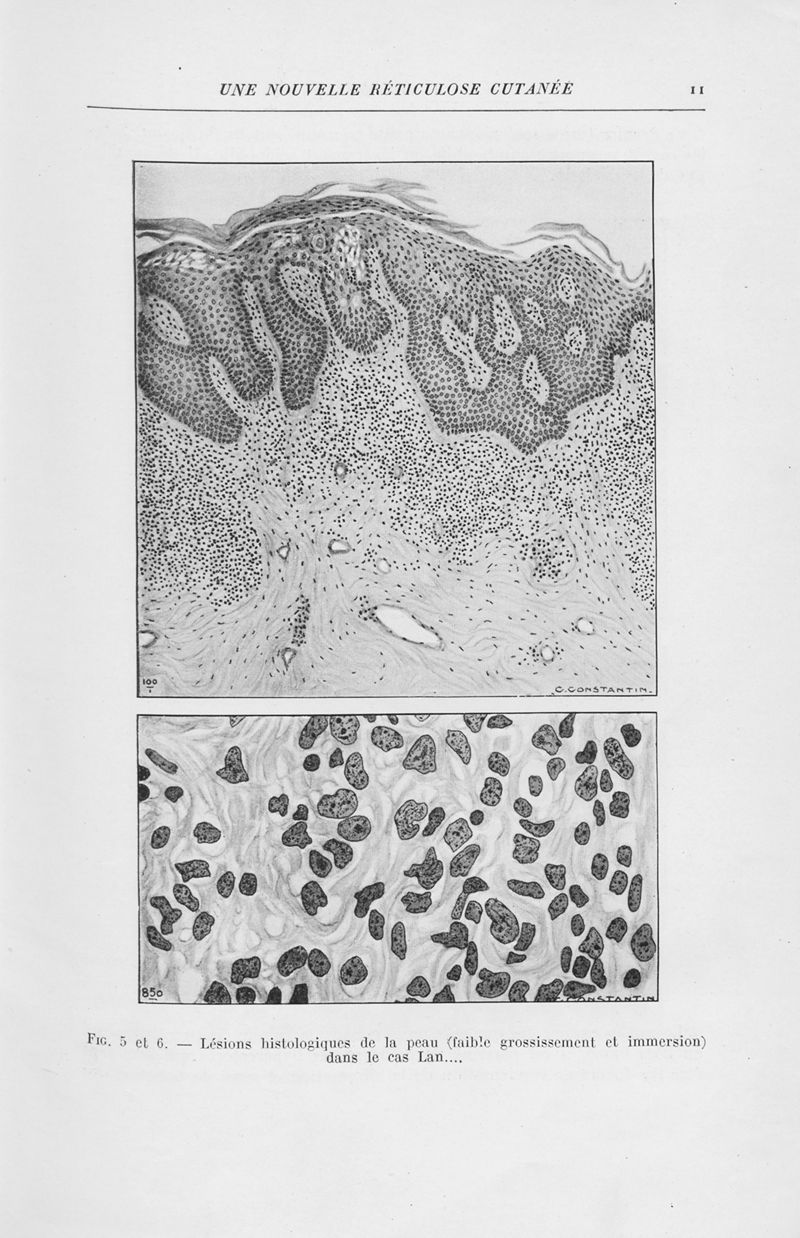

Annales de dermatologie et de syphiligraphie

8ème série, tome IX. - Paris : Masson, 1949.